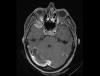

Varón de 60 años de edad con antecedente personal de hipertensión arterial y hábitos tabáquico y etílico severos. El paciente es ingresado por un cuadro de aproximadamente siete meses de evolución consistente en cefalea holocraneal...

Neurología: NeurooncologíaEtiología: NeoplasiasDiagnóstico final: Gliosarcoma cerebral con metástasis múltiples en neuroejeNivel de certeza: